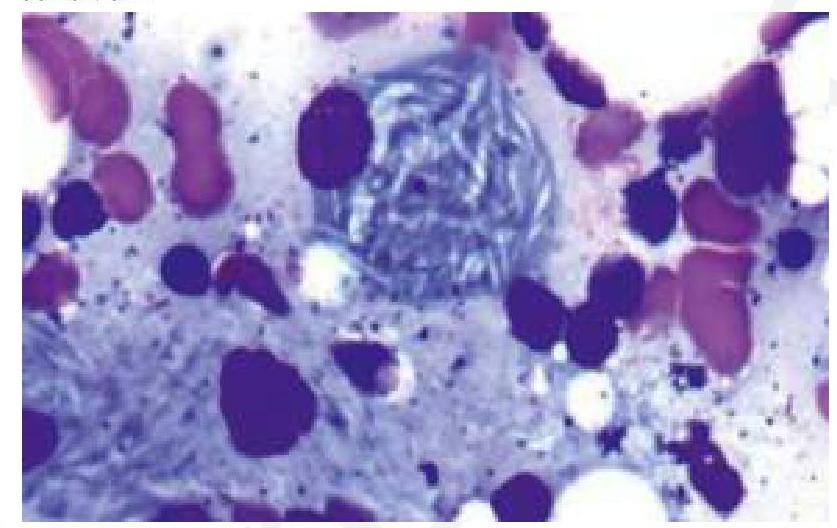

A child presents with bone pain and hepatosplenomegaly, indicative of Gaucher's disease. A trephine biopsy and aspirate show the following finding. Which of the following is the most likely enzyme deficient in this condition?

Explanation: ***Correct: Glucocerebrosidase*** - The clinical presentation of **bone pain**, **hepatosplenomegaly**, and the characteristic histological finding of **lipid-laden macrophages** (Gaucher cells) with a **crinkled paper** appearance in the bone marrow aspirate are highly suggestive of **Gaucher's disease**. - **Gaucher's disease** is caused by a deficiency of the lysosomal enzyme **glucocerebrosidase**, leading to the accumulation of **glucocerebroside**. *Incorrect: Hexosaminidase* - Deficiency of **hexosaminidase A** is associated with **Tay-Sachs disease**, which presents with neurological degeneration but typically **lacks hepatosplenomegaly** and bone pain. - The histological findings in Tay-Sachs disease would show neuronal storage of **GM2 gangliosides**, not Gaucher cells. *Incorrect: Sphingomyelinase* - Deficiency of **sphingomyelinase** causes **Niemann-Pick disease**, characterized by hepatosplenomegaly, neurological involvement, and interstitial lung disease, but the storage cells (foam cells) have a **foamy appearance** due to sphingomyelin accumulation, not the "crinkled paper" appearance of Gaucher cells. - While there is organomegaly, the distinct **histological features** in the image rule out Niemann-Pick disease. *Incorrect: Alpha 1,4-glucosidase* - Deficiency of **alpha 1,4-glucosidase** (acid maltase) causes **Pompe disease** (Glycogen Storage Disease Type II), which primarily affects muscle and liver with **glycogen accumulation**. - Pompe disease does not typically present with the same type of **bone pain** or the characteristic **Gaucher cells** seen in the image.